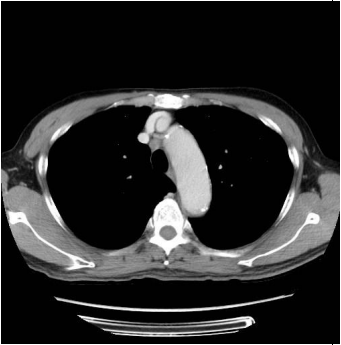

12. 71歲男性病人因為咳嗽三周,胸部X光意外發現左肺有陰影。電腦斷層檢查顯示(如圖示)左下葉有一顆腫瘤及右氣管前有一顆1公分淋巴結,頭部電腦斷層及骨骼掃描皆無異常。請問接下來的檢查何者最有效率,可以在最短的時間得到治療所需要的資訊? (A) 先做電腦斷層接片檢查確認為惡性後,再做正子斷層造影,淋巴結有異常再做縱膈腔鏡淋巴取樣。 (B) 先做電腦斷層接片檢查確認為惡性後,再做正子斷層造影,淋巴結有異常再做支氣管超音波經氣管淋巴結抽吸。 (C) 先做支氣管超音波周邊腫瘤切片,再做正子斷層造影。淋巴結有異常再做支氣管超音波經氣管淋巴結抽吸。 (D) 先做支氣管超音波經氣管淋巴結抽吸,確認為惡性腫瘤,如果為良性同時做支氣管超音波周邊腫瘤切片後,再考慮正子斷層造影。 (E) 先做正子斷層造影,確認無其他轉移再做電腦斷層切片檢查。